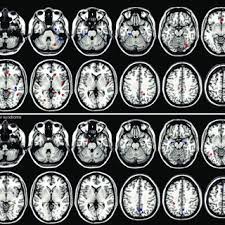

Pdf Can Asperger Syndrome Be Distinguished From Autism An Anatomic Likelihood Meta Analysis Of Mri Studies

Pdf Can Asperger Syndrome Be Distinguished From Autism An Anatomic Likelihood Meta Analysis Of Mri Studies from www.researchgate.net